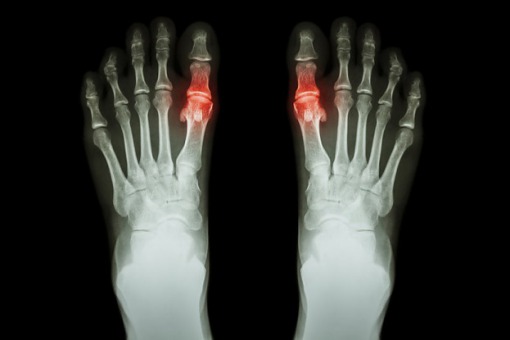

Dna moczanowa, jedno z najczęściej występujących zapaleń stawów, dotyka 2,5-5 proc. dorosłych....

Dna moczanowa to częsta choroba przewlekła, a jej odpowiednie monitorowanie zapobiega wystąpieniu...

Hyperurykemia i dna moczanowa związane są z większym ryzykiem współistnienia chorób...